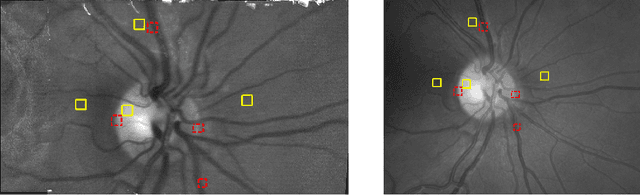

Abstract:The acquisition of high-resolution retinal fundus images with a large field of view (FOV) is challenging due to technological, physiological and economic reasons. This paper proposes a fully automatic framework to reconstruct retinal images of high spatial resolution and increased FOV from multiple low-resolution images captured with non-mydriatic, mobile and video-capable but low-cost cameras. Within the scope of one examination, we scan different regions on the retina by exploiting eye motion conducted by a patient guidance. Appropriate views for our mosaicing method are selected based on optic disk tracking to trace eye movements. For each view, one super-resolved image is reconstructed by fusion of multiple video frames. Finally, all super-resolved views are registered to a common reference using a novel polynomial registration scheme and combined by means of image mosaicing. We evaluated our framework for a mobile and low-cost video fundus camera. In our experiments, we reconstructed retinal images of up to 30{\deg} FOV from 10 complementary views of 15{\deg} FOV. An evaluation of the mosaics by human experts as well as a quantitative comparison to conventional color fundus images encourage the clinical usability of our framework.